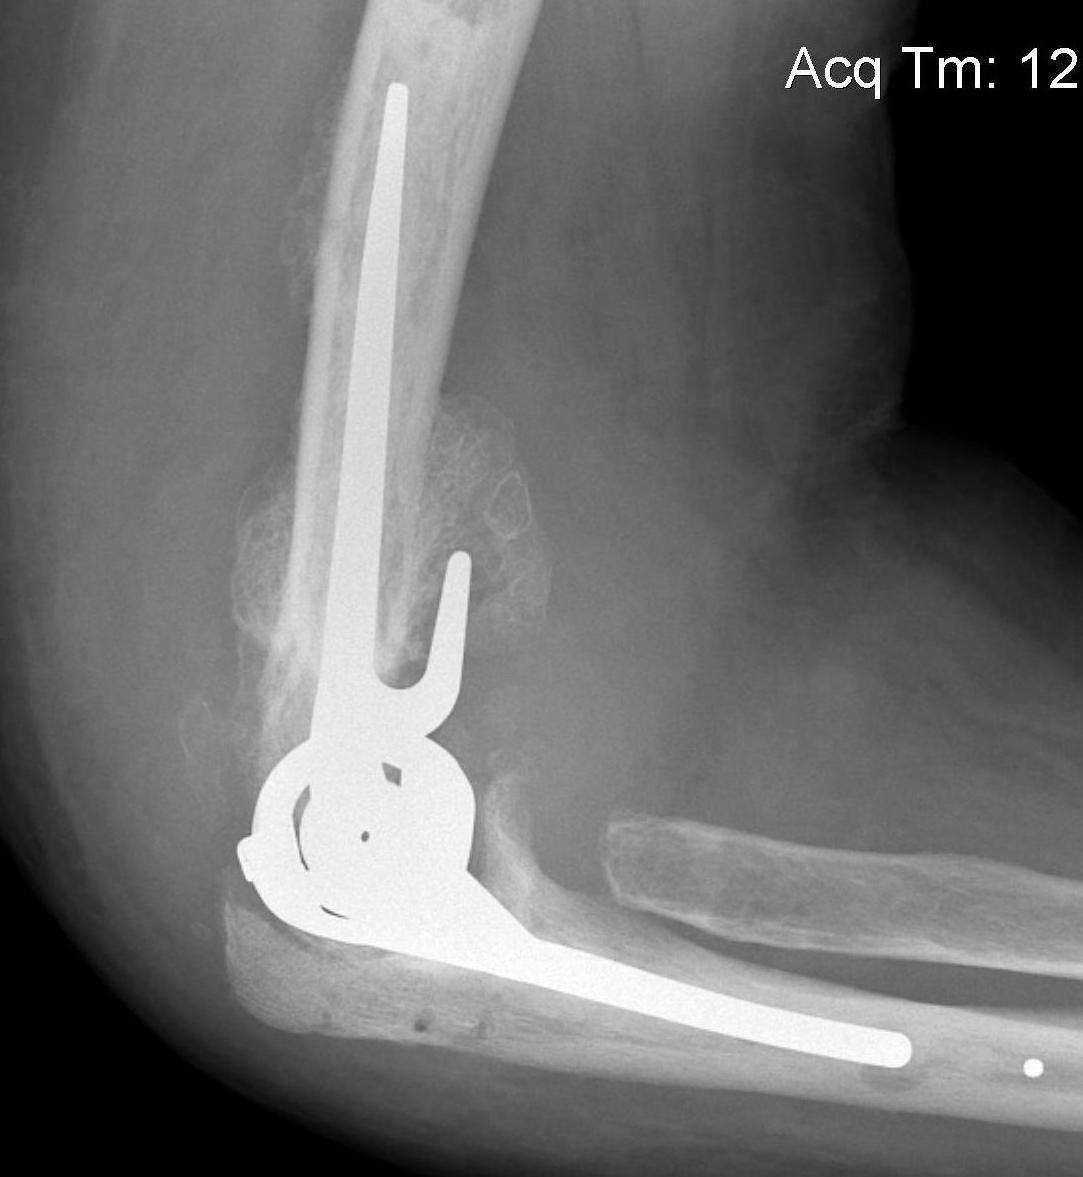

Total Elbow Arthroplasty

Issues

Infection

Triceps - must preserve triceps insertion

Bone stock - deficient humeral columns

Intra-operative fracture - ulna at risk

Constraint

- unlinked require collateral and triceps integrity

- semiconstrained - linked pin and bushing with anterior humeral flange

Results

- systematic review of 38 studies and 2118 patients with TEA for RA

- 7 year follow up

- implant failure 16%

- complication rate 25%

- young patients and unlinked design of TEA most at risk of aseptic loosening